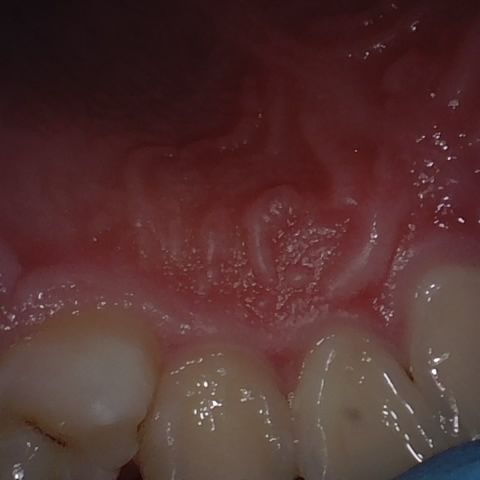

Annotated as "Good"